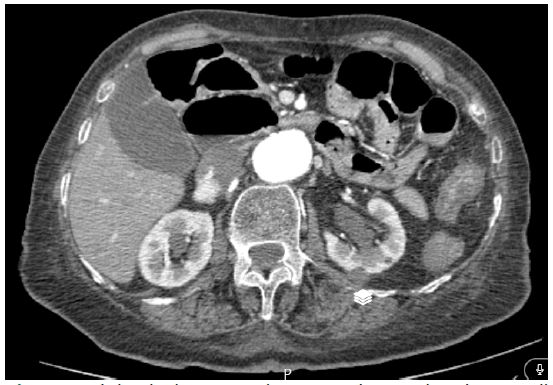

An 83-year-old female patient developed dyspnea after choking on her food. Her grandson, who was a physician performed HM on her and it successfully dislodged the airway obstruction. She did not develop any evidence of confusion but for further assessments was transported to the emergency room of our hospital. On arrival, the patient’s vital signs were stable, and she had no history of previous illnesses except long-standing dysphagia and epigastric pain on swallowing. Because she complained of shortness of breath, computed tomography was obtained (Figure 1), and it revealed a mild reticular change at the bases of the lungs and a large aneurysm at the entrance of the thoracic to the abdominal aorta. The patient was hospitalized with the diagnosis of aspiration pneumonia and treated with IV Ceftriaxone plus Clindamycin and was discharged after 3 days. Two weeks later, the patient returned due to a decreased level of consciousness and increasing shortness of breath and was hospitalized and treated again with the diagnosis of pneumonia. Also, a pulmonary CT-angiography was performed which was negative for pulmonary thromboembolism. In both hospitalizations, due to an aortic aneurysm, it was recommended not to undergo HM in case of recurrent aspiration.

Figure 1: Abdominal computed tomography Imaging show a mild reticular change at the bases of the lungs and a large aneurysm at the entrance of the thoracic to the abdominal aorta.